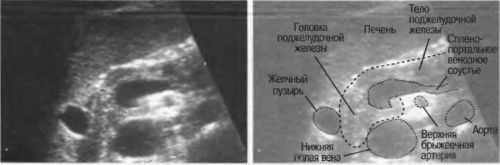

Поджелудочная железа на УЗИ

При отсутствии аномалий железа располагается в области эпигастрии и имеет следующие признаки:

- Форма. Поджелудочная имеет вытянутую форму и по своему внешнему виду напоминает головастика.